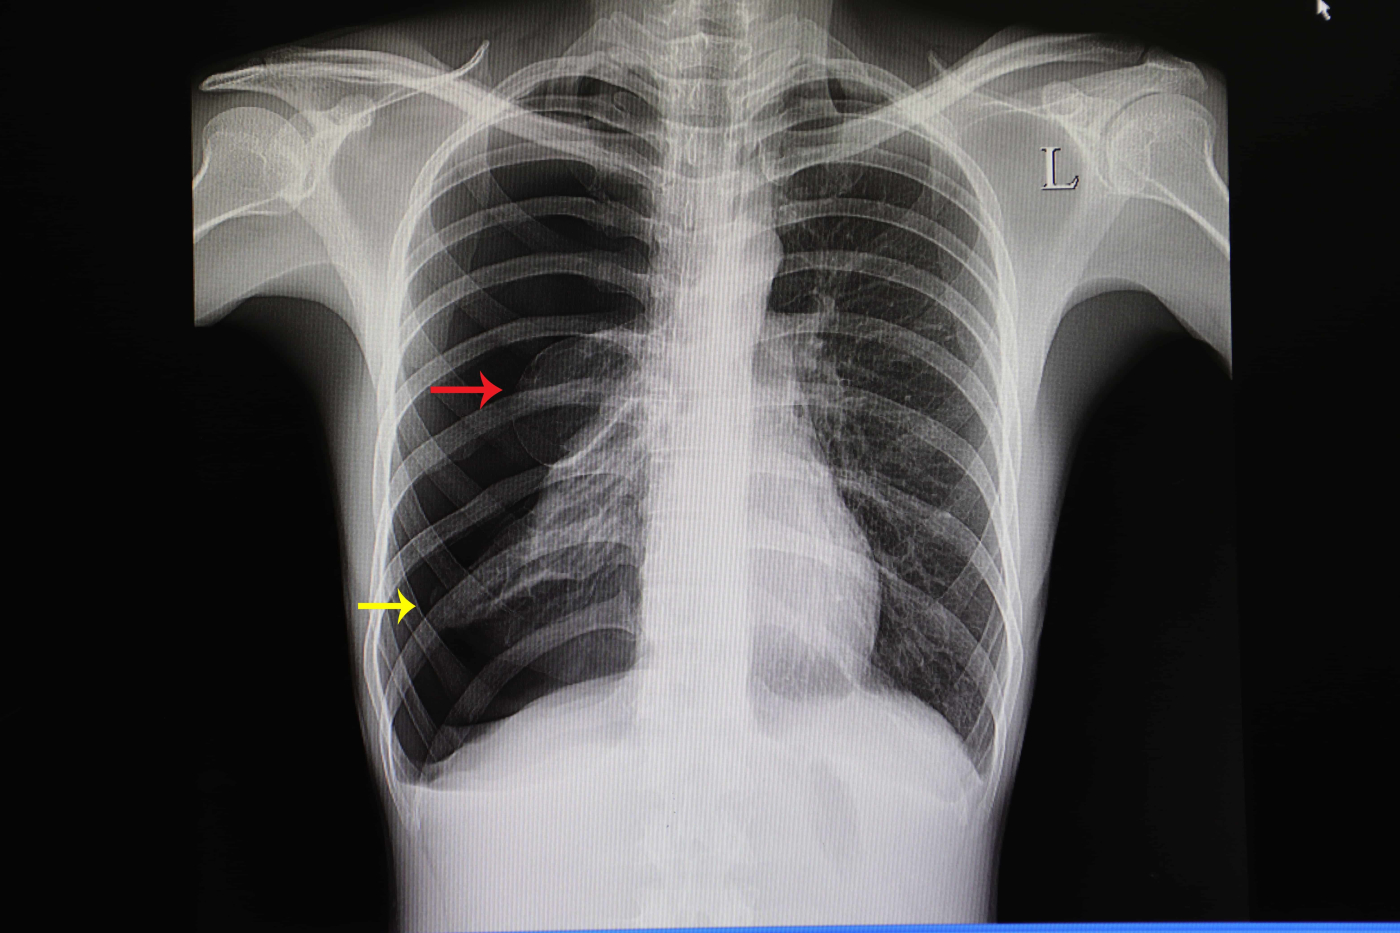

Doktor anda akan menyemak sejarah perubatan anda dan melakukan pemeriksaan fizikal. Doktor anda akan mendengar bunyi pernafasan melalui stetoskop. X-ray dada boleh mendiagnosis pneumothorax. Di samping itu, doktor akan memeriksa paras oksigen darah anda dan jantung dengan menggunakan ECG untuk menentukan sama ada anda mempunyai pneumothorax atau tidak.